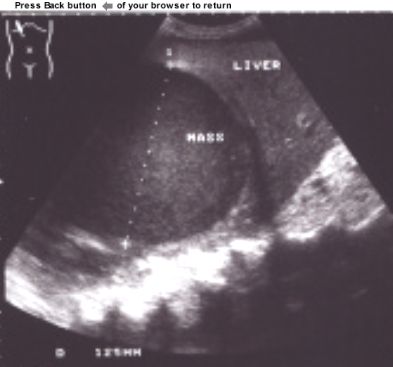

CASE

1:

This patient had an

abdominal ultrasound. A single, round,

hypoechoic, homogeneous, well

defined mass was demonstrated in the right liver lobe. The size of the

mass was 12,5 cm. The borders of the mass was smooth and clearly separated

from liver parenchyma. The rest of the liver parenchyma was normal and

examination of the rest of the abdomen did not reveal any other

pathology.

ANSWER:

Liver

Abscess